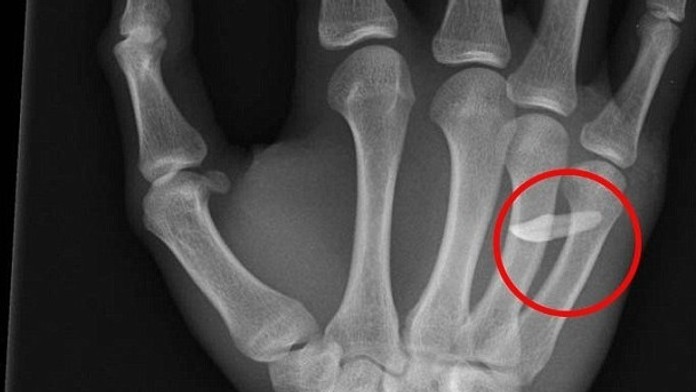

Röntgen odhalil príčinu opuchu. Mladík mal v ruke zub

Tínedžer lekárom tvrdil, že o cudzom predmete v ruke ani netušil.

Mladík prišiel do nemocnice s bolesťami a opuchnutou rukou. Röntgen odhalil, že medzi kostičkami prstov mal zub. Tínedžer lekárom tvrdil, že o cudzom predmete v ruke ani netušil.

Mladý muž (19) z britského West Sussex sa priznal doktorom, že nechtiac udrel svojho brata. Netušil však, že prišiel o zub. Brat mu mal nečakane skočiť do rany, keď doma udieral do boxovacieho vreca. Mladší súrodenec po rane tak plakal, že si ani neuvedomil, že prišiel o zub.

Ranu si mladík umyl a viac tomu nevenoval pozornosť. Až na druhý deň sa zobudil s veľkým opuchom a bolesťou. Lekári mu v nemocnici pichli tetanovku, dali antibiotiká a ranu vyčistili roztokom. Zub mu nakoniec z ruky vytiahli. Podľa denníka DailyMail sa zotavuje a nehoda mu nespôsobila žiadne následky.